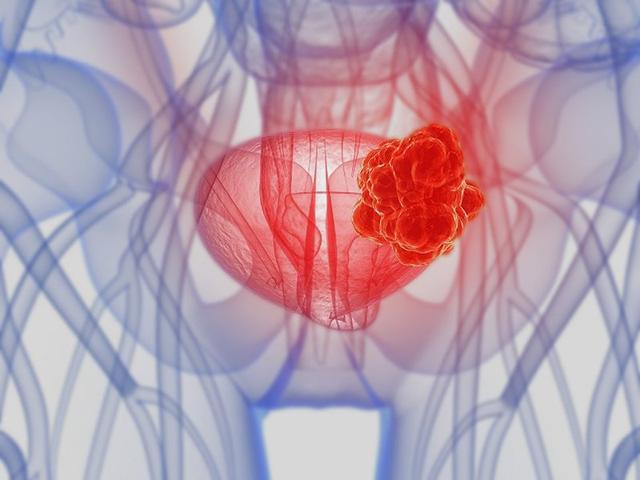

膀胱癌晚期會哪些症狀出現?

患有4期膀胱癌意味著什麼?第4階段是癌症的最晚期階段。在這個階段,癌細胞通常會擴散到疾病的原始位置以外的其他器官。

當膀胱癌到達第4階段時,原始腫瘤經常生長並推動膀胱壁。癌細胞可能已經擴散到靠近膀胱的器官或更遠的器官,例如肝臟或肺部。於是其症狀可能包括: